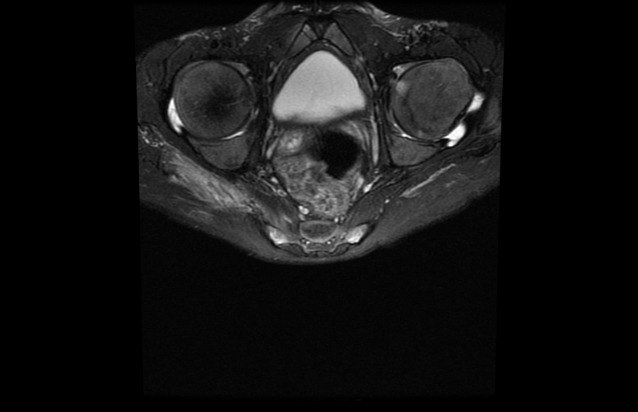

Hypopituitarism is a clinical syndrome that occurs when the anterior pituitary gland fails to secrete one or more hormones. Developmental delay is frequently seen in these patients. However, skeletal deformities and postural instability are unexceptional. We present a 17-year-old male patient with panhypopituitarism (PHP) with back and leg pain, postural malalignment, and skeletal deformities referred by the pediatric endocrinology clinic. According to the physical examination, laboratory tests, and radiographic assessments, the patient was considered as sequela spondyloarthropathy (SpA). Autoimmune and rheumatic diseases are frequently encountered in patients with hypogonadism. However, the association of PHP and ankylosing spondylitis (AS) has not yet been demonstrated. This case was presented to draw attention to the alignment of PHP and SpA and also to emphasize that skeletal deformities were not encountered in the absence of anterior hypophysis hormones.